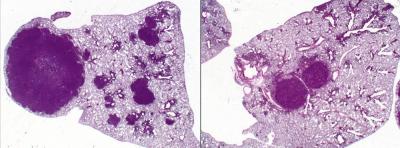

Now, in a new study in the journal Cancer Cell , Shaw and a team of scientists at the Salk Institute for Biological Studies found that phenformin, a derivative of the widely-used diabetes drug metformin, decreased the size of lung tumors in mice and increased the animals' survival. The findings may give hope to the nearly 30 percent of patients with non-small cell lung cancer (NSCLC) whose tumors lack LKB1 (also called STK11).

That led Shaw and his team to a class of drugs called biguanides, which lower cellular energy levels by attacking the power stations of the cell, called mitochondria. Metformin and phenformin both inhibit mitochondria; however, phenformin is nearly 50 times as potent as metformin. In the study, the researchers tested phenformin as a chemotherapy agent in genetically-engineered mice lacking LKB1 and which had advanced stage lung tumors. After three weeks of treatment, Shaw and his team saw a modest reduction in tumor burden in the mice.

Continuing the study between Salk and UCLA, Shaw and Shackelford coordinated teams in both locations to perform further testing on mice with earlier stage disease, using cutting-edge imaging technologies just like those used on lung cancer patients in the clinic. They found that early phenformin treatment causes increased survival and slower tumor progression in tumors lacking LKB1, but had no significant benefit for tumors with alterations in other lung cancer genes. This specificity in treatment fits with an emerging approach in cancer treatment nationwide, known as personalized medicine, in which the therapies for each patient are selected based on the genes altered in their tumors.